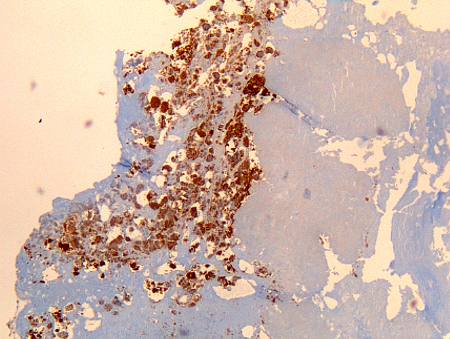

Coxiella burnetii chronic lymphadenitis: immunohistochemistry. Note the isolated infected cell (monocytes/macrophages) in the lymph node. Brown coloration identifies bacteria in monocytes/macrophages

Hubert Lepidi, Institut Hospitalo-Universitaire Méditerranée Infection